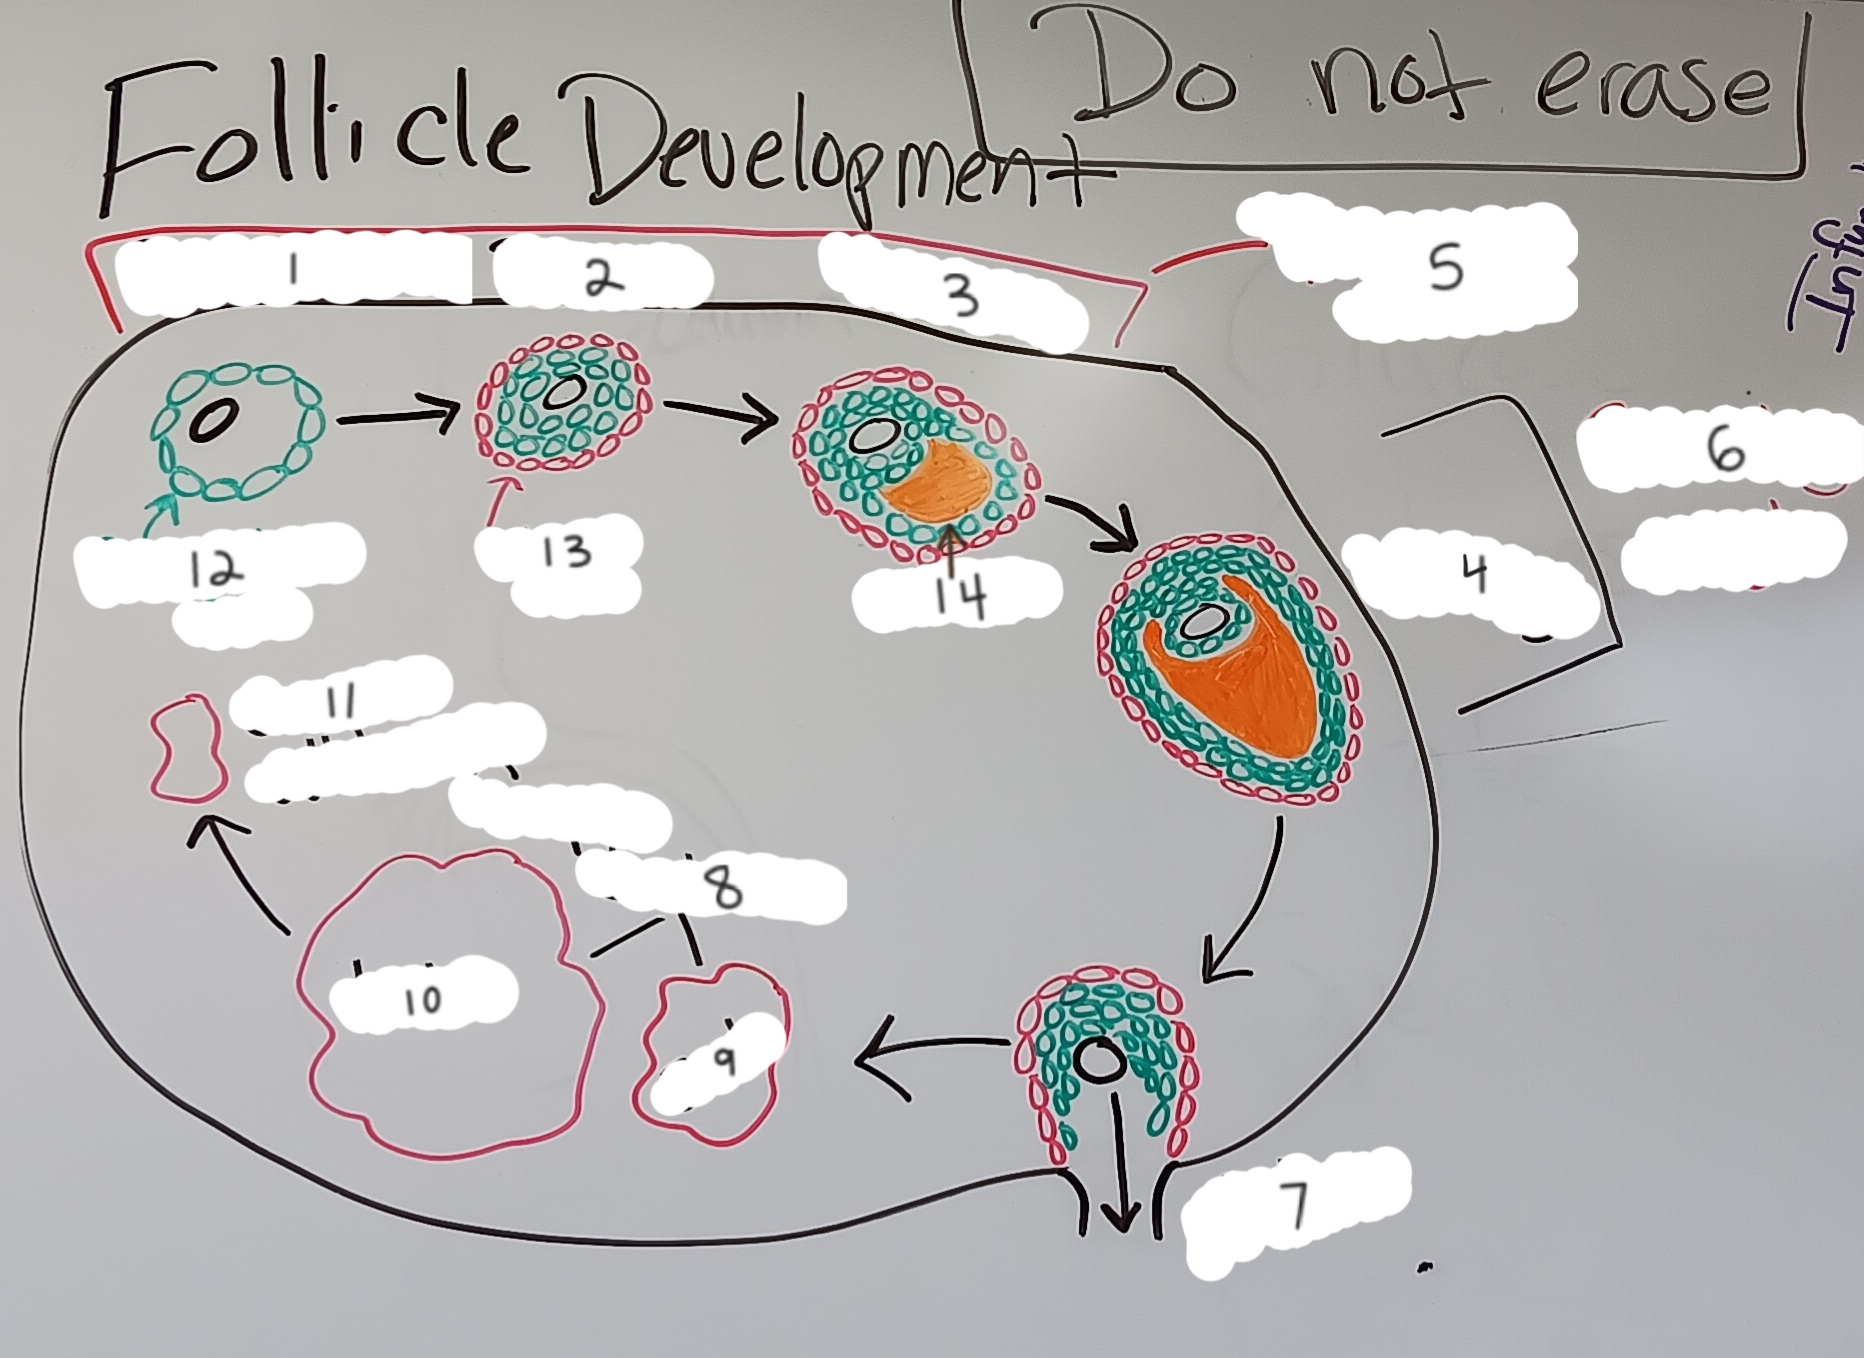

Primordial follicle

1

Primordial follicle

Primordial follicle

1

Primary follicle

2

Primary follicle

Primary follicle

2

Secondary follicle

3

Secondary follicle

Secondary follicle

3

Tertiary follicle

4

Tertiary follicle

4

Mature follicle

5

Mature follicle

Mature follicle

7

Antrum

10

Zona pellucida

9

Theca folliculi

8

Corona radiata

Corpus luteum

Corpus luteum

Corpus albicans

Corpus albicans

corpus luteum

8

early corpus luteum

9

late corpus luteum

10

corpus albicans

11

granulosa cells

12

theca cells

13

antrum

14